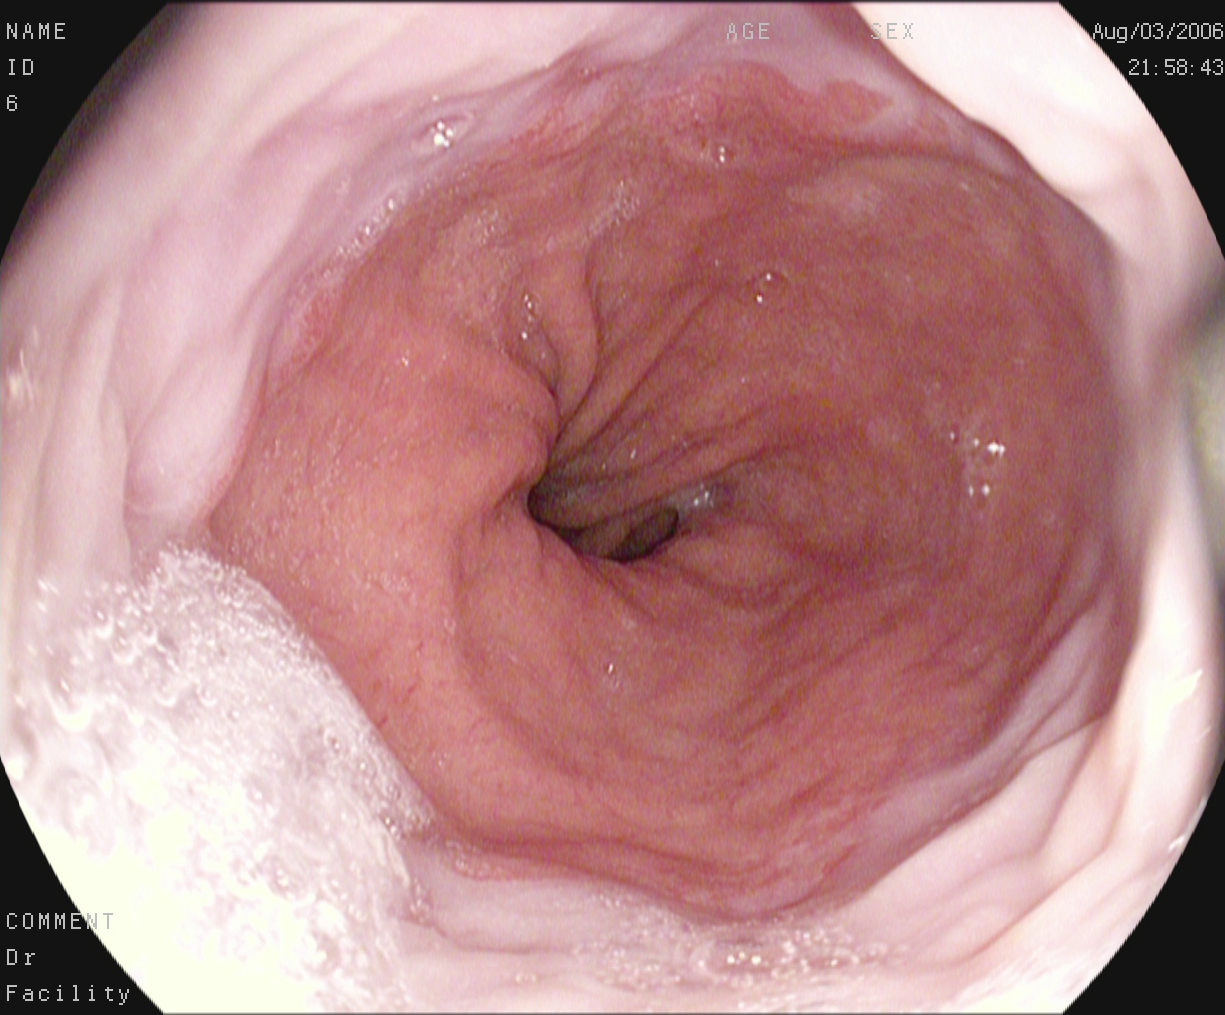

Figure 1. Sample images of GI findings. Each image represents one of the 16 classes from the dataset used for the Medico 2018 challenge (Pogorelov et al., 2017c, a).